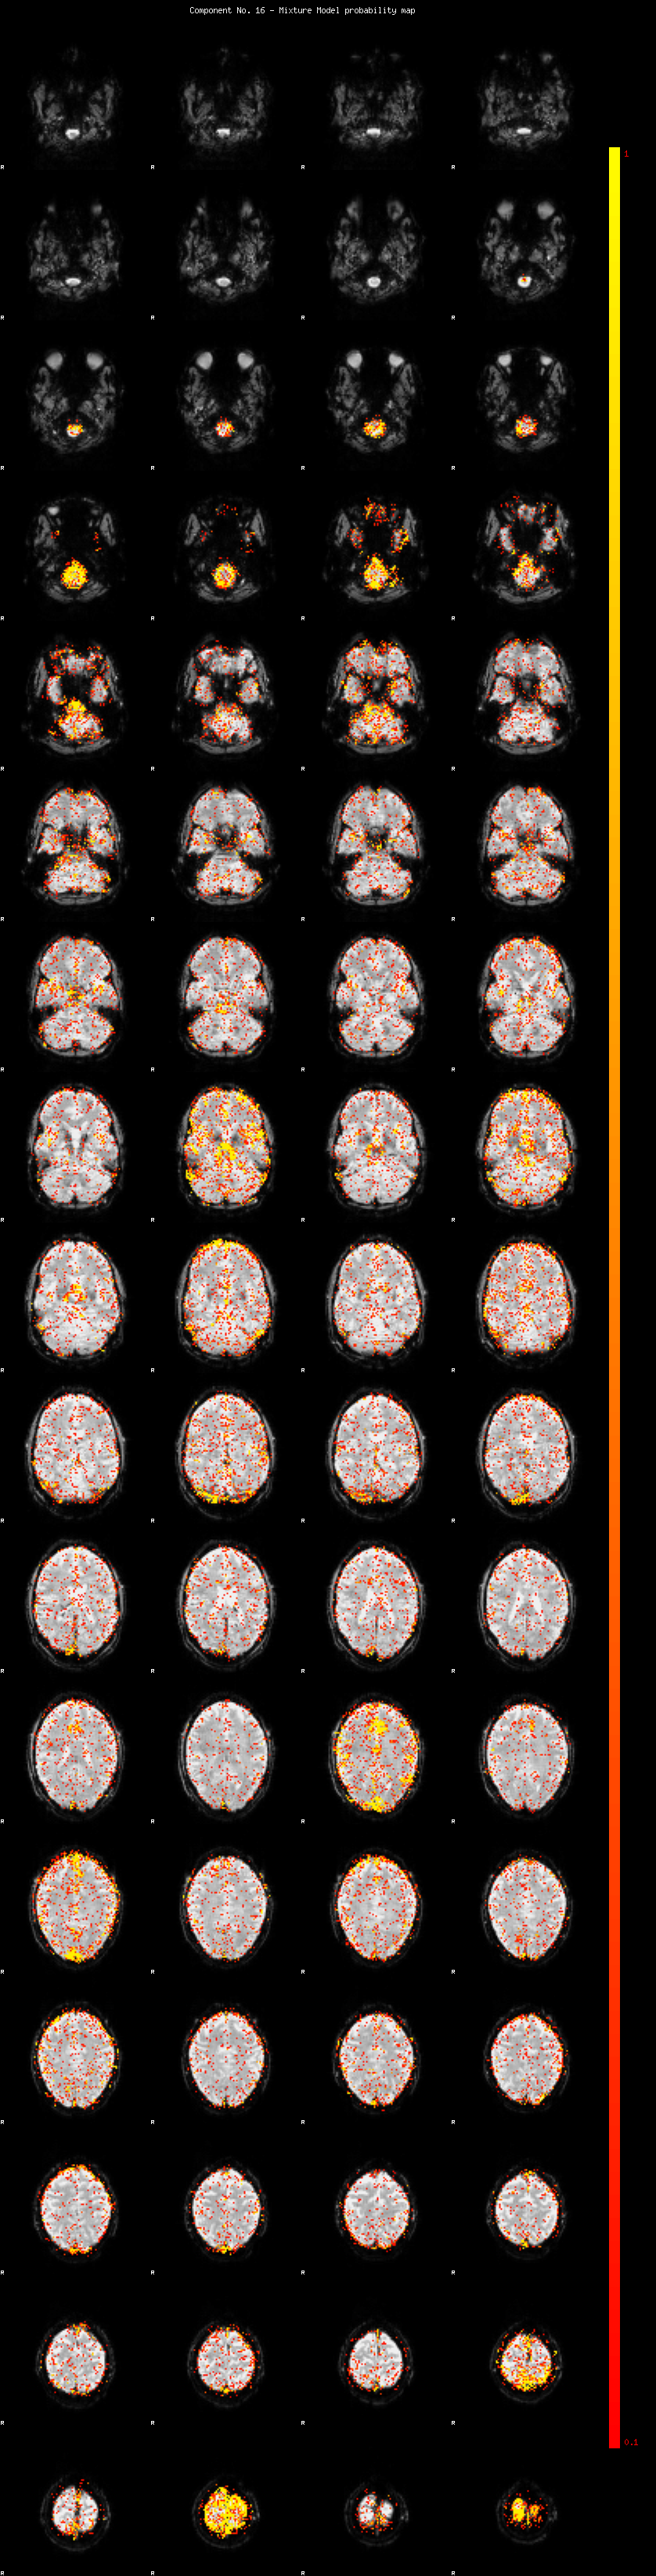

IC_16 Mixture Model fit

Means : -0.000000 3.056889 -2.619884

Vars : 1.000000 4.156003 2.475208

Prop. : 0.915765 0.043173 0.041063